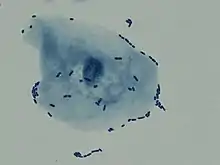

Multiple white cells seen in the urine of a person with a urinary tract infection using microscopy

Multiple bacilli (rod-shaped bacteria, here shown as black and bean-shaped) shown between white blood cells in urinary microscopy. These changes are indicative of a urinary tract infection.

In straightforward cases, a diagnosis may be made and treatment given based on symptoms alone without further laboratory confirmation.[4] In complicated or questionable cases, it may be useful to confirm the diagnosis via urinalysis, looking for the presence of urinary nitrites, white blood cells (leukocytes), or leukocyte esterase.[50] Another test, urine microscopy, looks for the presence of red blood cells, white blood cells, or bacteria. Urine culture is deemed positive if it shows a bacterial colony count of greater than or equal to 103 colony-forming units per mL of a typical urinary tract organism. Antibiotic sensitivity can also be tested with these cultures, making them useful in the selection of antibiotic treatment. However, women with negative cultures may still improve with antibiotic treatment.[4] As symptoms can be vague and without reliable tests for urinary tract infections, diagnosis can be difficult in the elderly.[11]